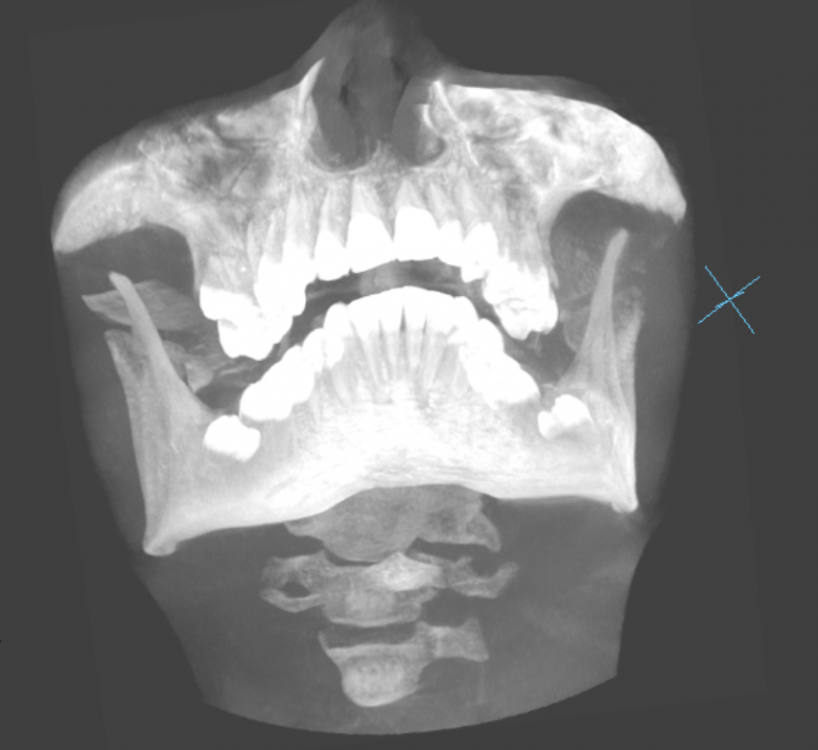

Faggott Опубликовано 3 мая, 2022 Автор Поделиться Опубликовано 3 мая, 2022 01.05.2022 в 21:50, Irouil сказал: Покажите КТ @Irouil, ссылка на DICOM-файлы из КТ: https://drive.google.com/file/d/1zzESnhJBWdFfQzYsPNaK6rfdAGsnEAcu/view?usp=sharing А это скрины 8-к (хотя я не уверена, что это нужные скрины) //было бы так хорошо, если бы мне кто-то раньше сказал, что КТ бесплатно высылают на почту (и высылают образ диска с программами и файлами, а не "файлы, которые вы сами открыть не сможете") и что на факультете, где есть ЭВМ и древние компы с линуксом, нет компов с дисководами //зато теперь у меня есть диск, который мне, к сожалению, некуда вставлять Ссылка на комментарий

Faggott Опубликовано 2 июля, 2022 Автор Поделиться Опубликовано 2 июля, 2022 Сегодня мне удалили 8-ки. На это ушло 40 минут, примерно 10 (у меня сбито ощущение времени без часов, так что это очень приблизительный срок) из которых мы ждали действия анестезии. Анестезия уже отошла, и с языком всё просто прекрасно. Как и с остальными частями лица. Даже ничего не болит (из-за пакетика Нимесила, возможно). //а ещё мне дали классный кусок льда в синей грелке. не знаю, сильно ли это поможет, но я прикладываю его на 15 минут с промежутком в час. очень увлекательное занятие Вот и они: 3 Ссылка на комментарий